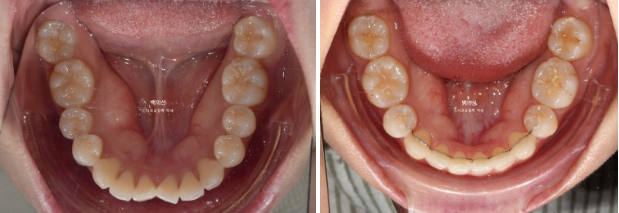

발치공간은 다 닫힌 것 처럼 보이지만 치실이 헐렁하게 들어가는 정도의 미세공간은 남아있습니다.

미진한 부분들을 개선하기 위해서 추가장치 재제작에 들어갔고 24년 9월부터 25년 4월까지, 25개의 추가장치를 다 낀 후 모습입니다.

25.04

모든 게 좋지만 환자분의 요구사항은 왼쪽 앞니 하나가 기울어져 것이었습니다.

이 부분을 해결하고자 추가장치를 한 번 더 쓰기로 합니다. 25년 5월부터 7월까지 10개의 추가장치를 더 낀 후 드디어 치료를 마무리 했습니다.